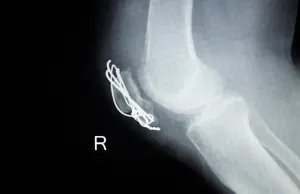

- Imaging Studies: X-rays or CT scans evaluate implant placement and bone healing.

Hardware Failure

Hardware failures, such as breakage or loosening, can compromise bone stability and function.

- Imaging Tests: Assess implant integrity and its effect on the surrounding bone.

- Surgical Removal or Replacement: A new implant may be required to restore structural support.